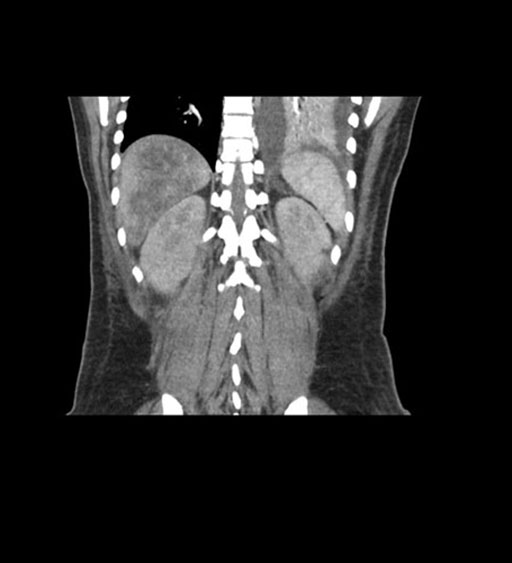

Coronal Arterial

Coronal Venous